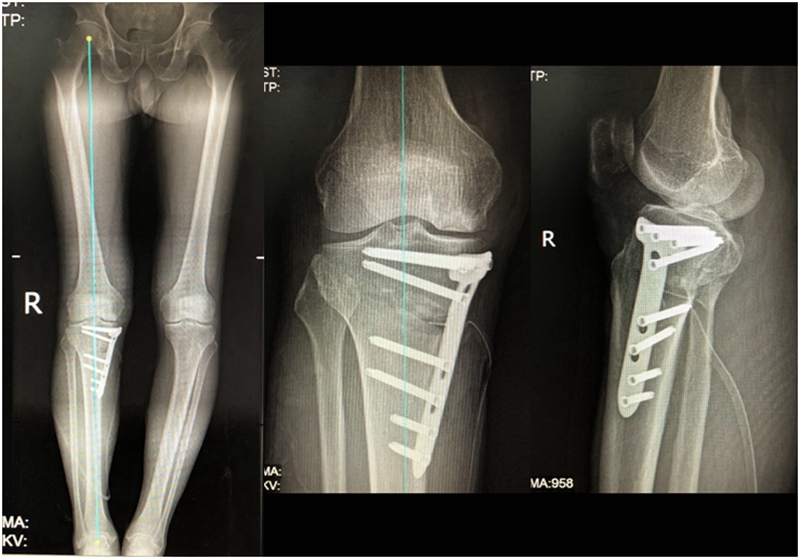

病例1:男,64岁,主诉左膝关节内侧疼痛6年余。MR提示骨坏死区占比为33.28%,矢状位病变区域前后径为26.42mm,半月板相对突出百分比(RPE)31.78%,同时存在胫骨侧来源的下肢内翻畸形(MPTA83°),关节线会聚角2°。

行关节镜检查+软骨摘除+微骨折+HTO术,术后随访2年恢复良好,活动自如,行走时无左膝关节疼痛不适。